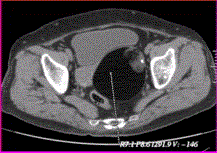

问题 患者女,36岁,CT发现盆腔内囊实性肿块,以囊性为主,含脂肪和钙化(下图),诊断应首先考虑为

选项 A.卵巢单纯囊肿 B.囊性畸胎瘤 C.卵巢囊腺瘤 D.卵巢囊腺癌 E.卵巢子宫内膜异位囊肿

答案 B